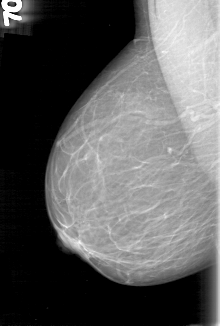

D_4060_1.LEFT_MLO

LEFT_MLO LINES 5326 PIXELS_PER_LINE 3361 BITS_PER_PIXEL 12 RESOLUTION 43.5 OVERLAY